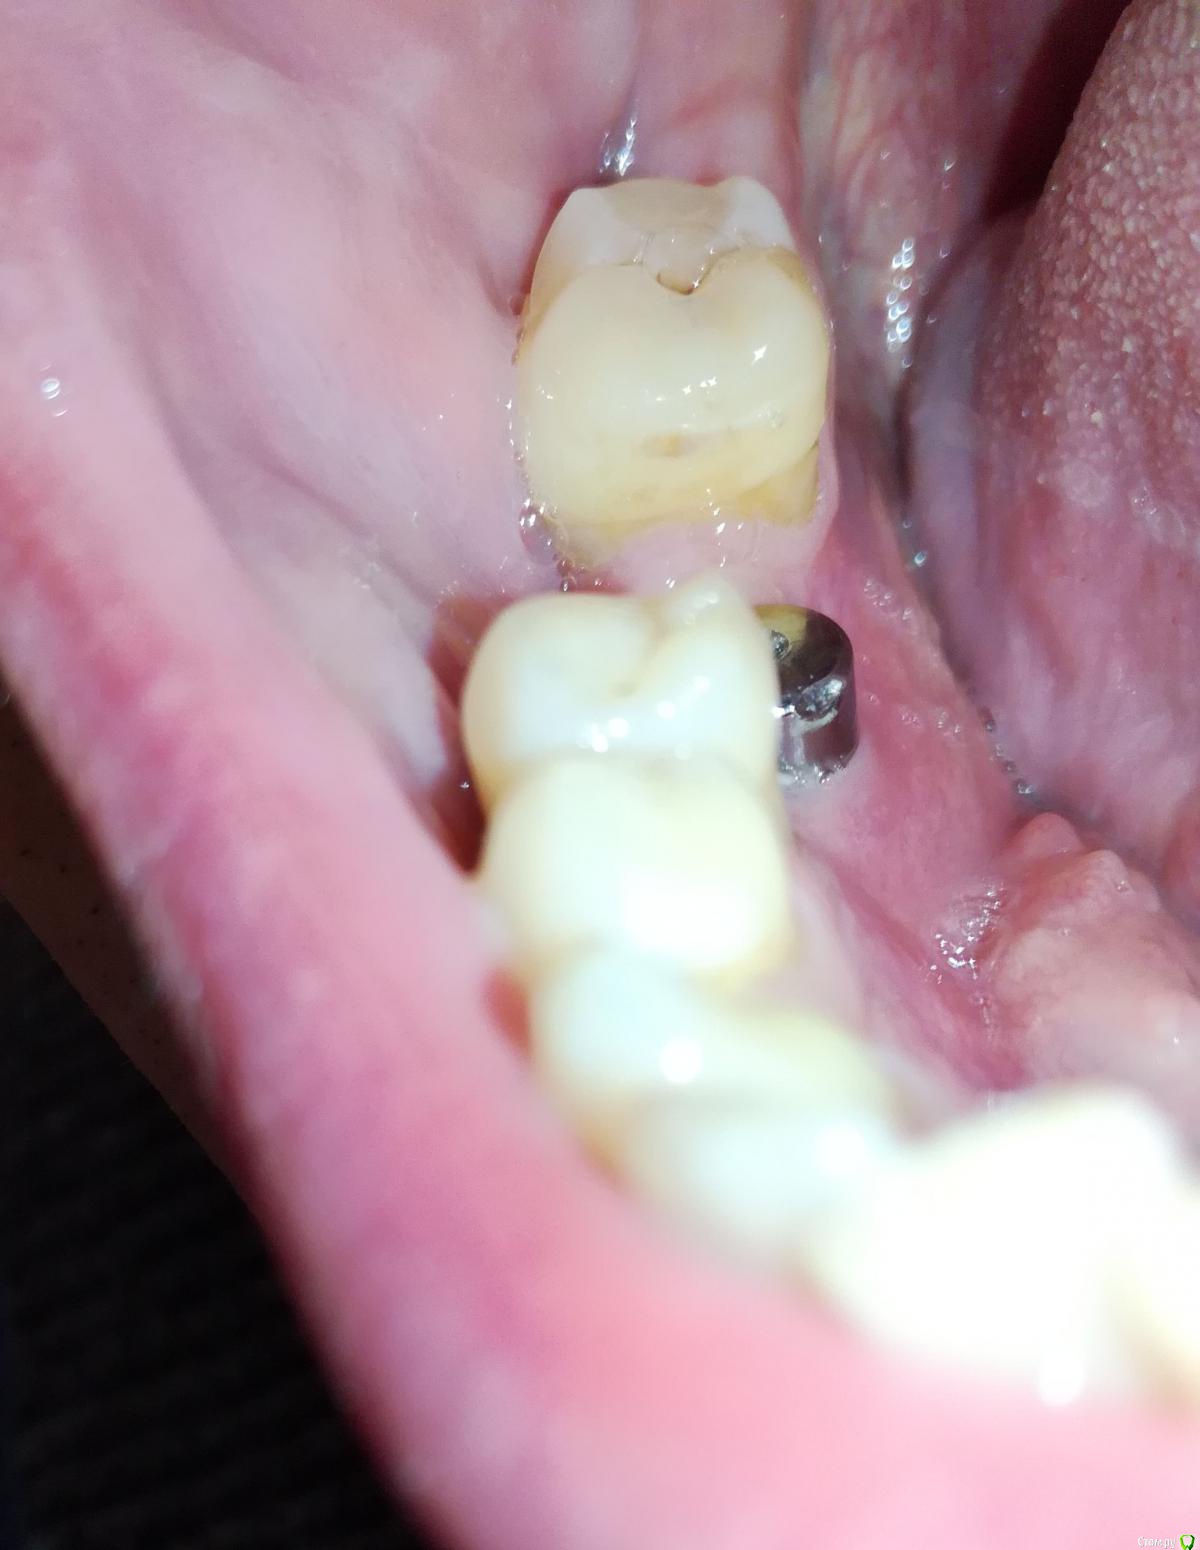

Alex19_73 Опубликовано 15 февраля, 2017 Поделиться Опубликовано 15 февраля, 2017 Доброго времени суток!Оцените пожалуйста качество имплантации и последующего протезирования. Имплантация проводилась с расщеплением гребня, имплант оказался смещен внутрь относительно других зубов. Хотел металлокерамическую коронку на винте, но ортопед сказал что возможно поставить только на цементе т.к. имплант сильно смещён внутрь. Вчера установили коронку но после дома стал разглядывать и она мне совсем не понравилась. По ощущениям очень неприятна, громоздка, когда жуешь то же как то не как родной зуб, языки щека постоянно по ней трут. С обратной стороны коронки обнаружил что то белое, наверно цемент, зубочисткой и ирригатором снять не удалось. Ортопед обратную поверхность зуба ковырял крюком счищая цемент. Это белое спускается с коронки прямо на десну.Можно ли если это цемент счистить его не испортив керамику коронки? Не может ли спровоцировать переимплантит такое затекание цемента, и вообще насколько это профессионально и соответствует протоколам (работа имплантолога и ортопеда)? Заранее спасибо. Ссылка на комментарий

Alex19_73 Опубликовано 17 февраля, 2017 Автор Поделиться Опубликовано 17 февраля, 2017 К сожалению снимок после имплантации пока не делал, сразу после имплантации врач делал томографию, но она есть наверно только на компьютере в клинике. Перед протезированием имплант был в хорошем (насколько я могу судить) состоянии под нагрузкой проверяли. Был вчера у ортопеда, оказалось что это не цемент а коронка, просто если смотреть спереди низ кажется светлее. Что бы уменьшить застревание еды хирург предложил бесплатно сделать пластику десны, с чем я согласился. Коронку снять не удалось, несмотря на значительные усилия в течении часа . Цемент mis. Пластику решили делать с установленной коронкой. Спасибо ответившим. Ссылка на комментарий